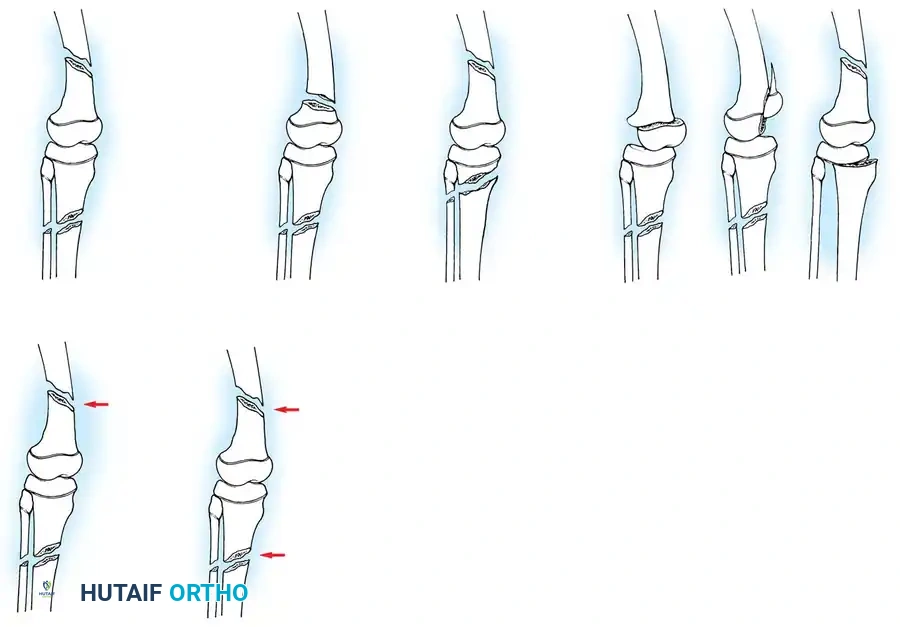

Salter-Harris Classifications and Variants

Canale and Shelton's extensive review of proximal tibial epiphyseal fractures highlighted that these injuries typically occur in older children (average age 14.2 years) approaching skeletal maturity.

- Type I and II Fractures: Most can be managed with closed reduction and a bent-knee cast. However, posterior displacement requires meticulous reduction to relieve arterial tension. Unacceptable angulation must be corrected; malunion in older children will not remodel sufficiently.

- Type III Fractures: These present in two distinct patterns:

- An intra-articular fracture analogous to an adult tibial plateau fracture.

- A fracture propagating through the tibial tuberosity physis, extending proximally across the epiphysis and into the knee joint.

Fig. 33-174: Salter-Harris type III fracture of the proximal tibia. A, Fracture analogous to a tibial plateau fracture. B, Fracture through the tibial tuberosity and across the epiphysis into the knee joint.

These tuberosity-extending fractures are not simple avulsions; they are massive, tongue-type Salter-Harris III injuries that lift the entire tibial tuberosity and anterior proximal physis superiorly. They almost universally necessitate open reduction and internal fixation (ORIF) to restore joint congruity and extensor mechanism continuity.

- Type IV Fractures: These cross both the epiphysis and metaphysis. They carry a high risk of growth arrest and joint incongruity. Stress radiographs are invaluable for diagnosing associated ligamentous instability, which may masquerade as a simple non-displaced physeal fracture.

Fig. 33-176: Physeal fracture with major ligamentous injury. A, Nondisplaced Salter-Harris type IV fracture. B, Stress radiograph shows fracture displacement and medial joint line opening, implying tibial collateral ligament injury. C, Intraoperative view during ORIF.

Triplane Variants: Variants of Salter-Harris III and IV fractures have been described as "triplane fractures of the proximal tibial epiphysis," analogous to the more common distal tibial triplane fractures. These occur during the transitional phase of physeal closure. If displaced, they require precise ORIF.

Fig. 33-177: Sagittal view of the knee depicting a coronal split fracture of the proximal tibia epiphysis through a partially closed physis.